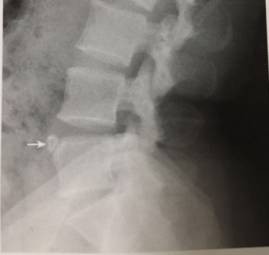

15、L5永存骨骺

男,32岁。L5前上角见孤立骨块,边缘光整,致密,对应区边缘亦致密。